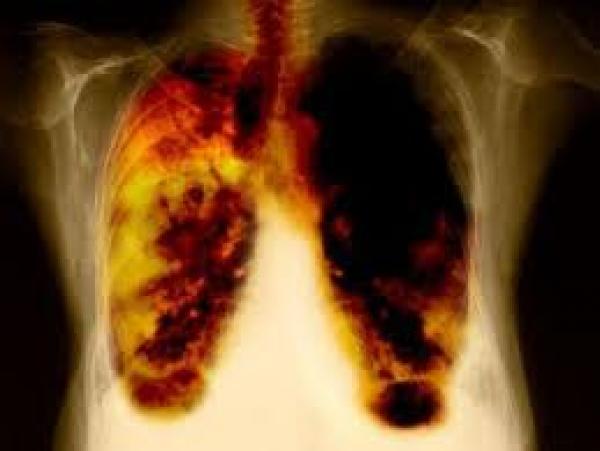

قالت منظمة الصحة العالمية يوم الأربعاء، إن سرطان الرئة يعد أكثر السرطانات التي تتسبب في وفاة الرجال في المغرب بنسبة 24.9 %، فيما تعتبر الإصابة بسرطان الثدي أكثر السرطانات التي تعرض النساء للوفاة.